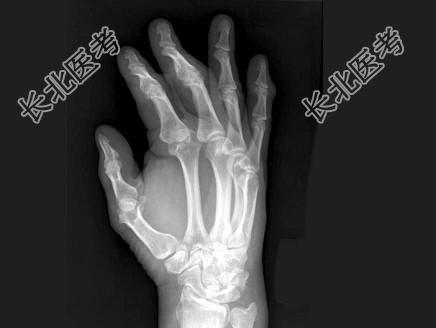

- 单项选择题男,24岁, 双手疼痛,结合图像, 最可能的诊断是 ( )

A、肢端肥大症

B、骨质疏松症

C、类风湿关节炎

D、痛风

E、维生素D缺乏症